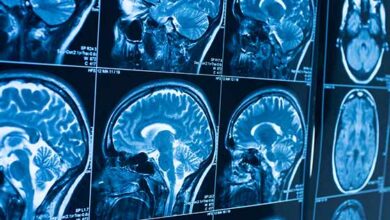

مغز و اعصاب